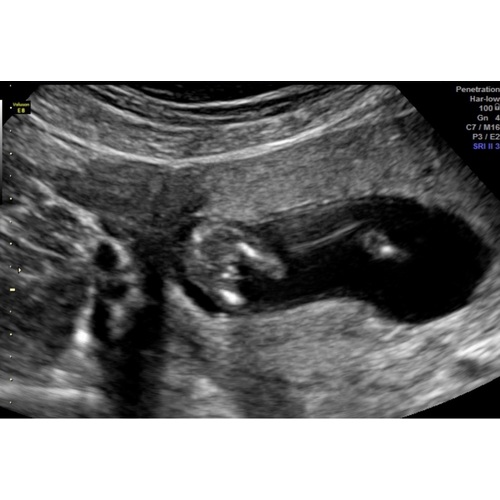

Boy or girl? Wat denken jullie? Ik vind reacties terug lezen en bij welke foto ze nou in de app horen nogal lastig dus hoop dat ik zie wat jullie van mijn foto vinden. Liefs